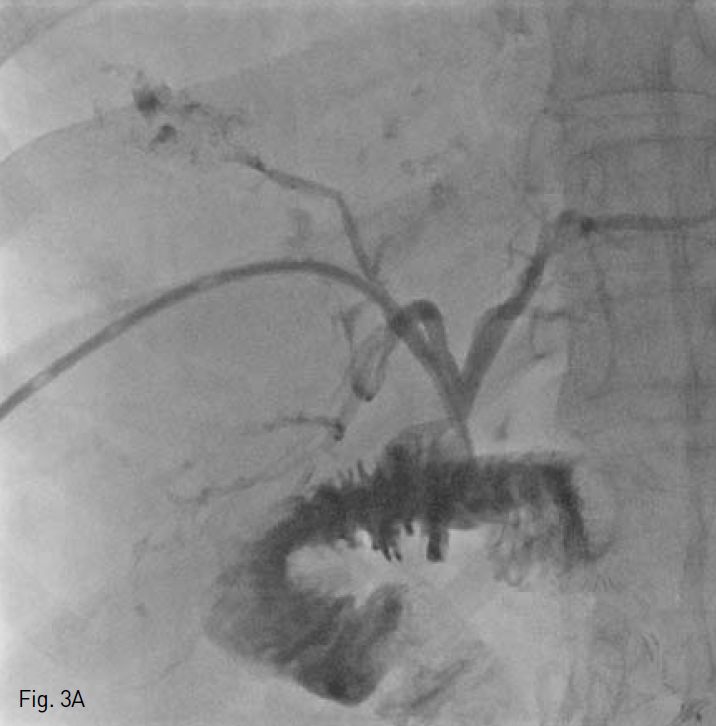

췌장 두부에 낭선종(Cystadenoma)으로 유문 보존 췌십이지장 절제술(PPPD)를 시행받은 환자로(Fig. 1A,B), 수술 2개월 후 지속적인 발열이 있어 내원하여 시행한 복부 전산화 단층 촬영상 간 우엽의 다발성 간농양과 함께 우엽 담관의 확장 소견이 보였고(Fig. 2), 경피경간 담도 배액술(PTBD)(Fig. 3A) 및 농양 배액술(Fig. 3B)을 시행받고, abscess content를 배양하여

시행한 병리학직 검사에서 E. coli가 연속해서 2차례 검출 되었다. 광범위항생제를 포함한 내과적 치료를 약 4개월 간 받았으며, 이후 증상의 호전을 보였고, 추적 관찰하여 시행한 복부 전산화 단층 촬영 상 대부분의 농양의 크기가 줄어늘고 특히 상대적으로 농양의 분포가 많았던 간우엽의 크기 감소와 꼬리엽의 보상적 비대가 보였다(Fig. 4). 더 이상 abscess content에 미생물 배양은 되지 않았으며, 퇴원하였다.

Fig. 3

Cholangiogram during right percutaneous biliary drainage A and cavitogram during percutaneous abscess drainage B show communications between abscess cavities and bile duct.